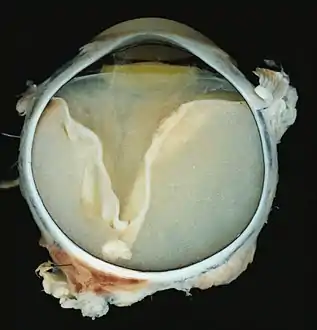

Pathology

Grossly, retinal detachment and yellowish subretinal exudate containing cholesterol crystals are commonly seen. Microscopically, the wall of retinal vessels may be thickened in some cases, while in other cases the wall may be thinned with irregular dilatation of the lumen.[10] The subretinal exudate consists of cholesterol crystals, macrophages laden with cholesterol and pigment, erythrocytes, and hemosiderin.[11] A granulomatous reaction, induced by the exudate, may be seen with the retina.[12] Portions of the retina may develop gliosis as a response to injury.

A case of Coats' disease, showing total retinal detachment with subretinal exudate containing cholesterol crystals and a fibrous nodule in the posterior pole